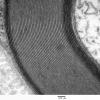

PERIPHERAL NEUROPATHY

3 NORMAL MYELIN & SCHWANN CELLS

1 Myelin